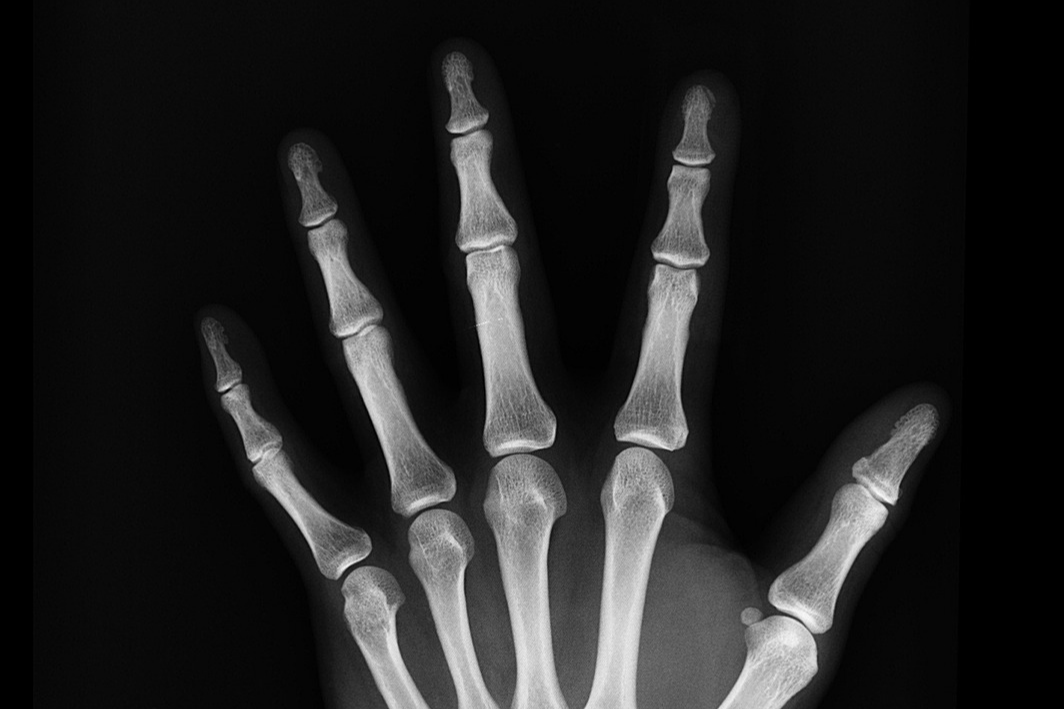

🔹 X-ray 촬영 후 골절 상태 확인

🔹 경미한 골절: 깁스(석고붕대) 또는 부목 착용

🔹 심한 골절: 수술 필요 (금속판, 나사, 핀을 이용한 고정술)

🔹 회복 기간: 약 6주~수개월 (뼈 상태에 따라 차이 있음)